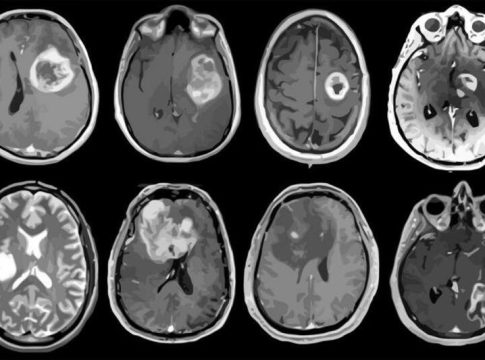

Desde la SEN advierten de que, este tipo de tumores que aglutinan más de 120 tipos en el sistema nervioso, en los últimos años se ha observado un incremento en el número de casos por año debido, principalmente, a la mejora de las técnicas de imagen -lo que ha permitido perfeccionar su diagnóstico-, y al progresivo envejecimiento de la población.

Y es que la edad de aparición de los tumores cerebrales presenta un pico en la edad pediátrica, pero también un aumento progresivo con la edad en adultos, hasta alcanzar su máximo de incidencia entre la sexta y la séptima década de la vida. Se estima que, en la actualidad, en España hay alrededor de 20.000 personas que padecen algún tipo de tumor cerebral, clasificado bien como un tumor primario (originado en el cerebro) o como un tumor metastásico (originado en otras partes del cuerpo, pero que se ha diseminado al cerebro).

Los tumores cerebrales suponen aproximadamente el 2% de todos los cánceres diagnosticados en adultos y el 15% de los diagnosticados en niños, lo que le convierte, durante la edad pediátrica, en el segundo tipo de cáncer más detectado después de la leucemia. En todo caso, aunque no son los tumores más frecuentes, tienen un alto impacto en la vida de las personas que los padecen.